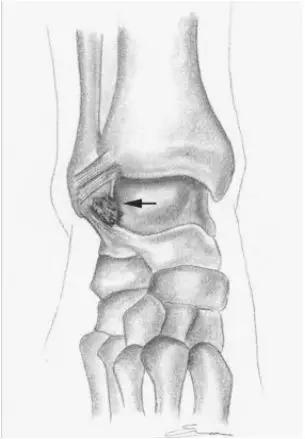

2.前踝撞击综合症:

- 又称足球踝,通常为骨性撞击,由于经常性背屈导致胫骨远端关节面前缘与距骨颈部上缘骨赘反复撞击,有时滑膜软骨瘤病的游离体聚积在关节囊前部也会导致前撞击综合症。

- 放射学表现主要为胫骨前下缘与距骨颈部前上缘鸟嘴样骨刺形成。

放射学表现主要为胫骨前下缘与距骨颈部前上缘鸟嘴样骨刺形成